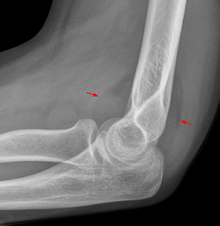

Fat pad sign: Ventral fat pad bowed and dorsal fat pad visible in a case of an undisplaced fracture of the radius head which is not visible directly.

On an elbow X-ray, the fat pad sign, also known as the sail sign, suggests an occult fracture. Its name derives from the fact that it has the shape of a spinnaker (sail).[1] It is caused by displacement of the fat pad around the elbow joint. Both anterior and posterior fat pad signs exist, and both can be found on the same X-ray.

In children, a posterior fat pad sign suggests a condylar fracture of the humerus. In adults it suggests a radial head fracture. The fat pad sign only occurs after an intra-articular fracture.

The fat pad sign is invaluable in assessing for the presence of an intra-articular fracture of the elbow. An anterior fat pad is often normal. However a posterior fat pad seen on a lateral x-ray of the elbow is always abnormal. The patient will be unable to flex their elbow and requires orthopaedic input.[2]

The posterior fat pad is normally pressed in the olecranon fossa by the triceps tendon, and hence invisible on lateral radiograph of the elbow.[3] When there is a fracture of the distal humerus, or other pathology involving the elbow joint, inflammation develops around the synovial membrane forcing the fat pad out of its normal physiologic resting place. This is visible as the "posterior fat pad sign" and is often the only visible marker of a fracture, particularly in the pediatrics population.